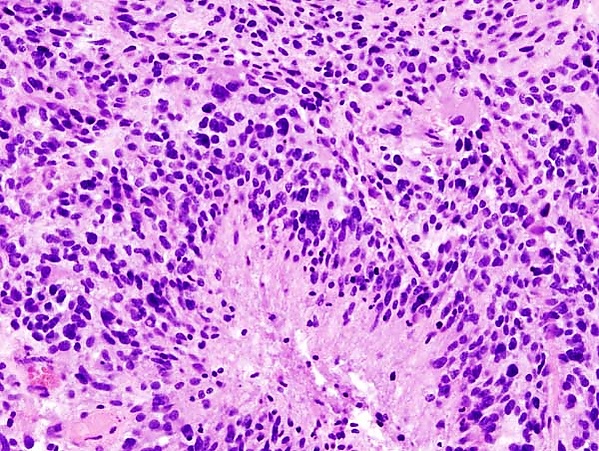

Микроскопически опухоль представлена диффузно-инфильтрирующими опухолевыми клетками с овальными или вытянутыми астроцитарными ядрами и вариабельным видом цитоплазмы и фибриллярных глиальных отростков. На периферии опухолевые клетки могут инфильтрировать ткань в виде диффузного одиночного паттерна, нередко с захваченными нейронами и аксонами. Клеточная морфология вариабельна даже в пределах одной опухоли: обычно присутствует смесь клеток с вытянутыми ядрами и тонкими фибриллярными отростками, клеток с эксцентричными ядрами и стекловидной эозинофильной цитоплазмой, крупных плеоморфных клеток и малых клеток со скудной цитоплазмой. Могут наблюдаться участки, напоминающие олигодендроглиому, а также миксоидный фон и микрокистоз. Митотическая активность, клеточность и ядерная атипия варьируют в зависимости от степени злокачественности[5].

Иммуногистохимическое исследование биоптата опухоли: астроцитомы иммуногистохимически характеризуются экспрессией глиального фибриллярного кислого белка, Olig2 и мутантного белка IDH1 (при наличии мутации R132H, составляющей 90 % всех IDH-мутаций). Пролиферативный индекс Ki67 возрастает с повышением степени злокачественности[5].